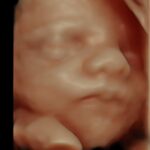

Sistema ecografico per ostetricia, ginecologia e fertilità

VOLUSON S8 con Touch panel

- 3D Uterine Trace

- Immagini veloci chiare e uniformi

- Dettaglio e risoluzione di contrasto eccezionale

- Visualizzazione dei piccoli vasi e dei bordi nel cuore fetale con RadiantFlowTM

- HDlive: tecnologia di rendering 3D/4D di Voluson che trasforma i dati ecografici in immagini più realistiche con profondità, illuminazione e texture migliorate